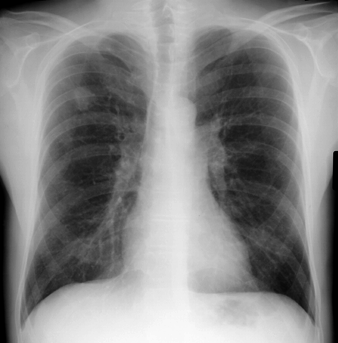

| CASO 1 Nodulo Pulmonar |